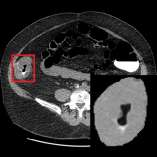

The elasticity of soft tissues has been widely considered as a characteristic property to differentiate between healthy and vicious tissues and, therefore, motivated several elasticity imaging modalities, such as Ultrasound Elastography, Magnetic Resonance Elastography, and Optical Coherence Elastography. This paper proposes an alternative approach of modeling the elasticity using Computed Tomography (CT) imaging modality for model-based feature extraction machine learning (ML) differentiation of lesions. The model describes a dynamic non-rigid (or elastic) deformation in differential manifold to mimic the soft tissues elasticity under wave fluctuation in vivo. Based on the model, three local deformation invariants are constructed by two tensors defined by the first and second order derivatives from the CT images and used to generate elastic feature maps after normalization via a novel signal suppression method. The model-based elastic image features are extracted from the feature maps and fed to machine learning to perform lesion classifications. Two pathologically proven image datasets of colon polyps (44 malignant and 43 benign) and lung nodules (46 malignant and 20 benign) were used to evaluate the proposed model-based lesion classification. The outcomes of this modeling approach reached the score of area under the curve of the receiver operating characteristics of 94.2 % for the polyps and 87.4 % for the nodules, resulting in an average gain of 5 % to 30 % over ten existing state-of-the-art lesion classification methods. The gains by modeling tissue elasticity for ML differentiation of lesions are striking, indicating the great potential of exploring the modeling strategy to other tissue properties for ML differentiation of lesions.